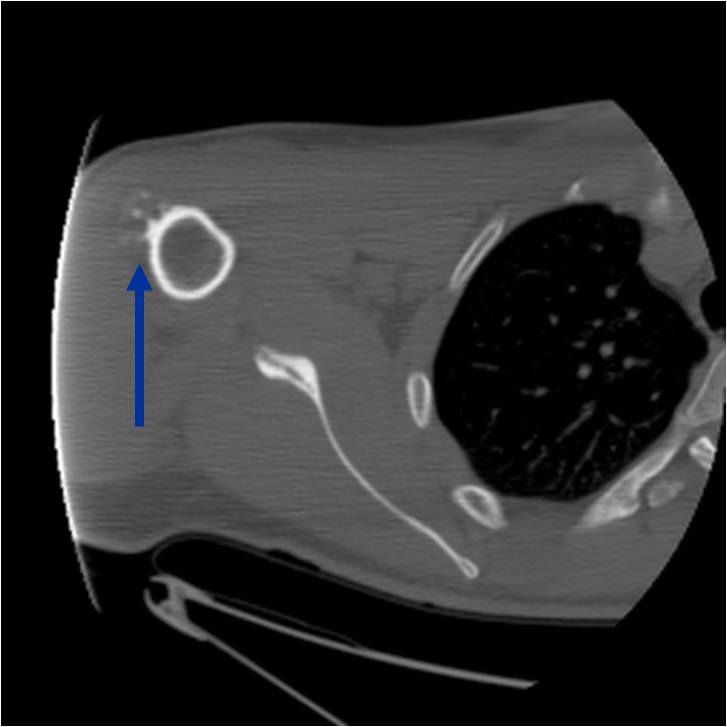

Radiographic Presentation

- Well circumscribed

- Appears to be embedded in underlying cortical bone

- Typically covered by a thin shell of reactive, often ossified periosteum

- Medullary cavity not grossly invaded

- Lobulated, obviously hyaline cartilage tumor

- Cartilaginous lobules separated by fibrous connective tissue or well-formed lamellar bone

- Calcium deposition occasionally present